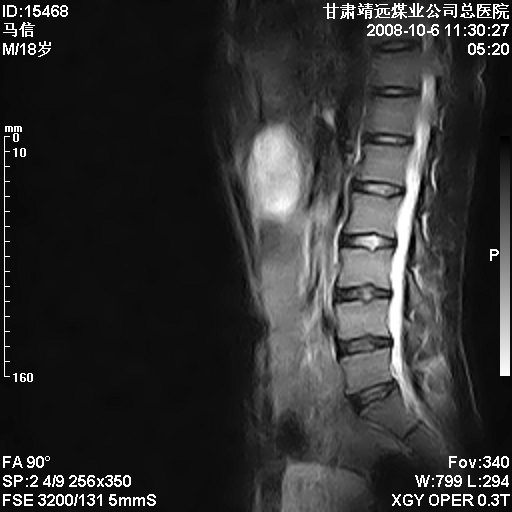

患者18岁,学生,在玩耍中受伤来检查,患者喜欢打篮球。颈椎内异常信号影,我们考虑占位,但是不像占位,又考虑硬膜囊的增厚,大家关建看颈椎椎管内的那个异常占位信号

腰椎的改变是不是正常发育的改变,还是打篮球的长期慢性损伤。

考虑 c3-4 c4-5 c5-6椎间盘突出,l3-4 l4-5 l5-s1椎间盘变性

颈椎建议做增强扫描;腰椎诸椎终板骨骺炎。

后纵韧带增厚,颈2/3、3/4、4/5、5/6椎间盘变性、突出;椎体有旋转,提示椎小关节有问题;腰椎间盘变性,许莫氏结节。

后纵韧带增厚,颈2/3、3/4、4/5、5/6椎间盘变性、突出;椎体有旋转,提示椎小关节有问题。腰椎诸椎体终板骨骺炎可能性大!支持!